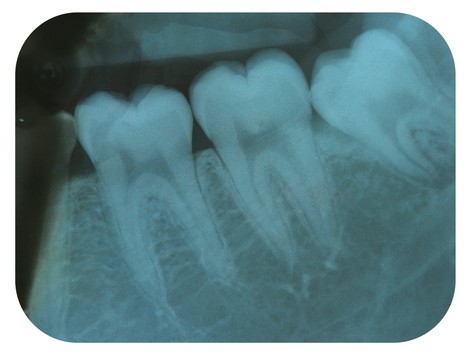

Rentgenodiagnostyka stomatologiczna odgrywa kluczową rolę w precyzyjnej ocenie stanu zdrowia zębów, kości szczęki, żuchwy oraz zatok szczękowych. Dzięki obrazowaniu radiologicznemu możemy wykryć zmiany niewidoczne gołym okiem, takie jak próchnica pod wypełnieniami, ubytki strukturalne, stany zapalne czy torbiele. Zdjęcia rentgenowskie są również niezbędne przy planowaniu leczenia ortodontycznego, implantologicznego oraz chirurgicznego.

W naszym gabinecie wykonujemy różne rodzaje zdjęć RTG, w tym:

• zdjęcia panoramiczne,

• zdjęcia punktowe,

• zdjęcia cefalometryczne.

Nasz sprzęt pozwala nam na uzyskanie obrazów o wysokiej rozdzielczości przy jednoczesnym minimalizowaniu dawki promieniowania. Zdjęcia wykonujemy zarówno w formie analogowej, drukowane na kliszy, jak i w wersji cyfrowej, zapisanej na płycie CD. Dzięki temu pacjenci mogą łatwo przechowywać i udostępniać wyniki badań lekarzom prowadzącym.